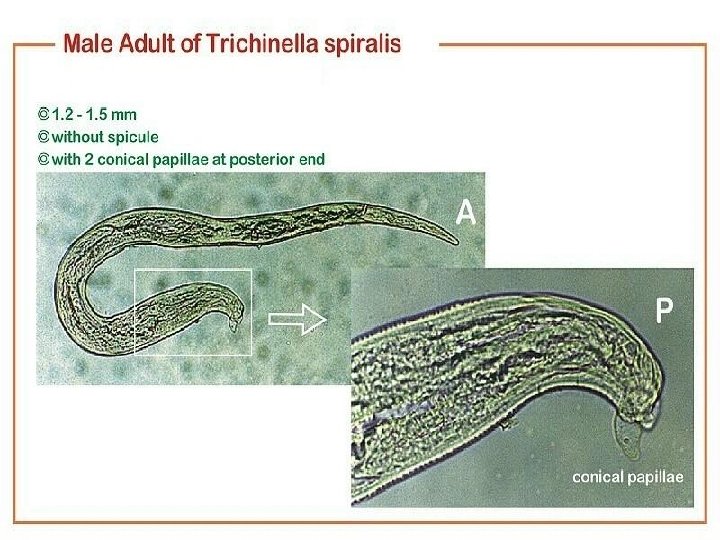

6 -Trichinella spiralis: b- Male: Small size Stichocytes With 2 conical papillae at posterior end.